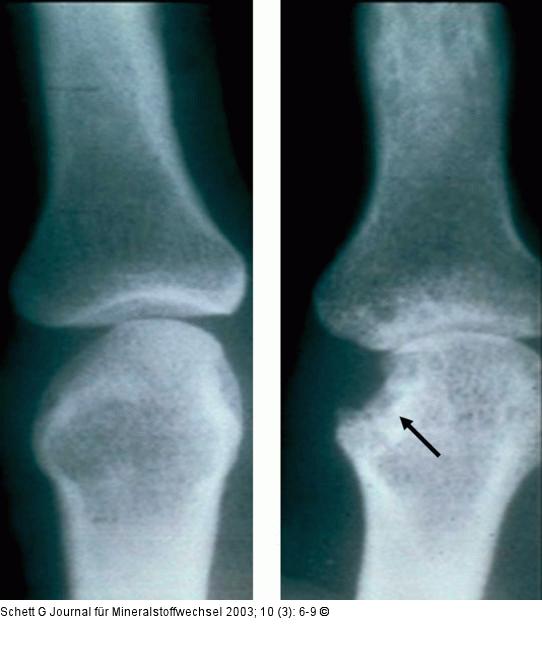

Abbildung 1: Rheumatoide Arthritis - Knochenerosion Röntgenbild einer lokalen Knochenerosion bei rheumatoider Arthritis. A. keine Erosion; B. lokale Knochenerosion (Pfeil). Auffallend ist die exzentrische Lokalisation der Veränderung, die der Schnittstelle von Knochen, Knorpel und Synovialmembran entspricht. Der subchondrale Knochen ist teilweise arrodiert und durch strahlentransparentes Entzündungsgewebe ersetzt. |

Abbildung 1: Rheumatoide Arthritis - Knochenerosion

Röntgenbild einer lokalen Knochenerosion bei rheumatoider Arthritis. A. keine Erosion; B. lokale Knochenerosion (Pfeil). Auffallend ist die exzentrische Lokalisation der Veränderung, die der Schnittstelle von Knochen, Knorpel und Synovialmembran entspricht. Der subchondrale Knochen ist teilweise arrodiert und durch strahlentransparentes Entzündungsgewebe ersetzt. |